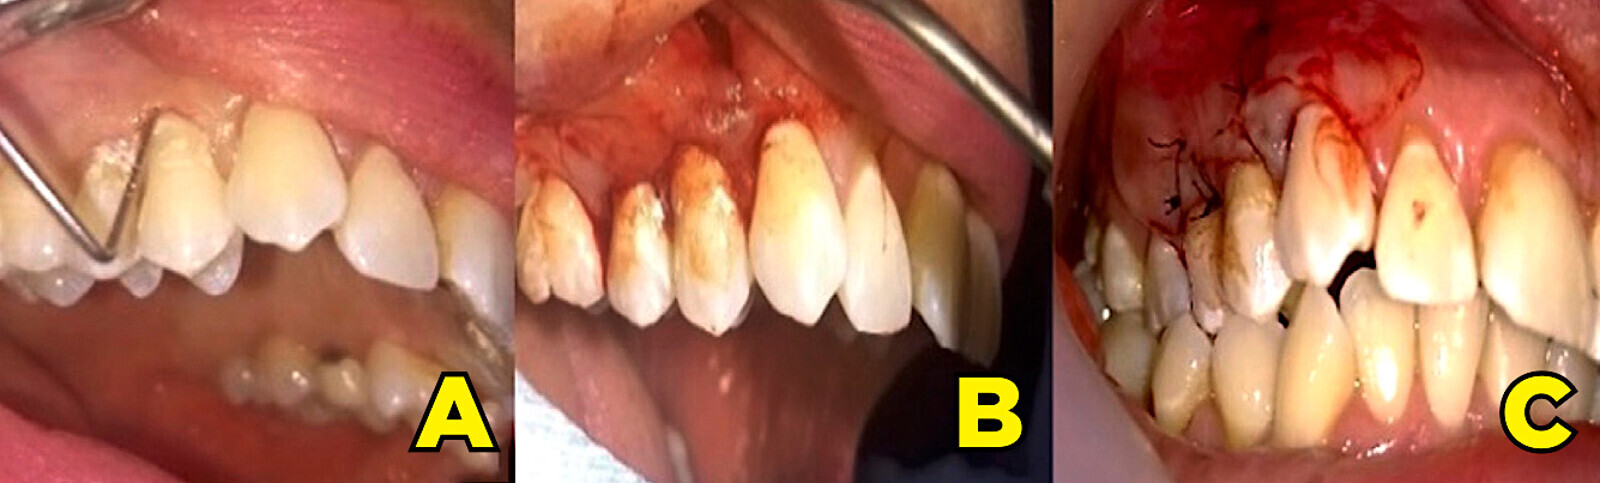

Figura 1. Fotografías iniciales del caso (A, B y C). Medición y registro de recesiones y lesiones LCNCs con sondeo (D, E y F). Evaluación de la lesión periapical en el diente 22 con superposición de aspecto tomográfico vestibular (E).

Paciente femenina de 37 años que se presentó a consulta refiriendo ligero malestar en el diente 22, posterior a un tratamiento de conductos después de 14 meses, el cual no presentaba signos inflamatorios en fondo de saco, ni fístula. Reportó además hiperestesia dentinaria en ambas arcadas tras la ingesta de alimentos atemperados y endulzados. En los datos generales de la historia clínica odontológica, manifestó no presentar antecedentes patológicos o hereditarios, no era fumadora, ni exfumadora, no bruxista; no reportó dietas con influencia de alimentos abrasivos-veganos o líquidos acidúricos, tampoco episodios de reflujo gastroesofágico3. Reportó utilizar para su higiene bucal personal cepillo de cerdas blandas (técnica de Bass), hilo dental y accesorios interproximales. A la inspección bucal armada se observaron y registraron restauraciones y prótesis con desajuste. En ambas arcadas se obserbvó una combinación masiva de recesiones y LCNCs. La inspección se complementó con sondeo periodontal y los datos de medición se agregaron en un periodontograma. El tamaño de las recesiones, el nulo sangrado al sondaje periodontal y la profundidad promedio de inserción 1 mm, nos informa de un periodonto reducido sin periodontitis (con recesiones gingivales)4.

La literatura menciona tres métodos para evaluar el grosor del fenotipo gingival de un diente defectuoso: la transparencia de la sonda dentro del surco gingival es el método más utilizado hoy en día, puesto que ha demostrado ser sencillo y eficaz para evaluar el espesor gingival5,6. Las recesiones fueron clasificadas según Miller y las LCNCs según la clasificación de Cairo7. En la interpretación radiográfica dentoalveolar del diente 22, se observó una zona radiolúcida difusa, circundante no definida, con material radiopaco extralimitando el ápice, determinando una periodontitis apical, derivada de tratamiento endodóntico deficiente, que requirió respaldo tomográfico. La paciente cooperó en todo momento y estuvo atenta para resolver este grupo de problemas que la aquejaba, señalando la preocupación por atenderlos de inmediato con expectativa positiva (Figura 1).